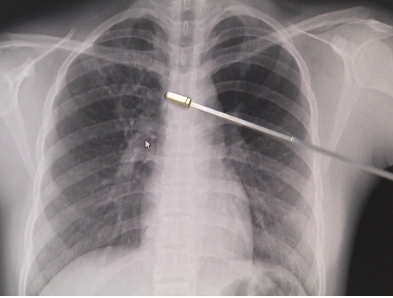

잠복결핵감염은 결핵간염검사에서 양성으로 판정되고 흉부 X선 검사 등 결핵검사를 실시하여 활동성 결핵이 제외된 경우 잠복결핵감염으로 진단합니다.

결핵은 증상 여부나 진찰, 흉부 X선 검사, 객담 결핵균 검사 등을 통해서도 확인합니다.